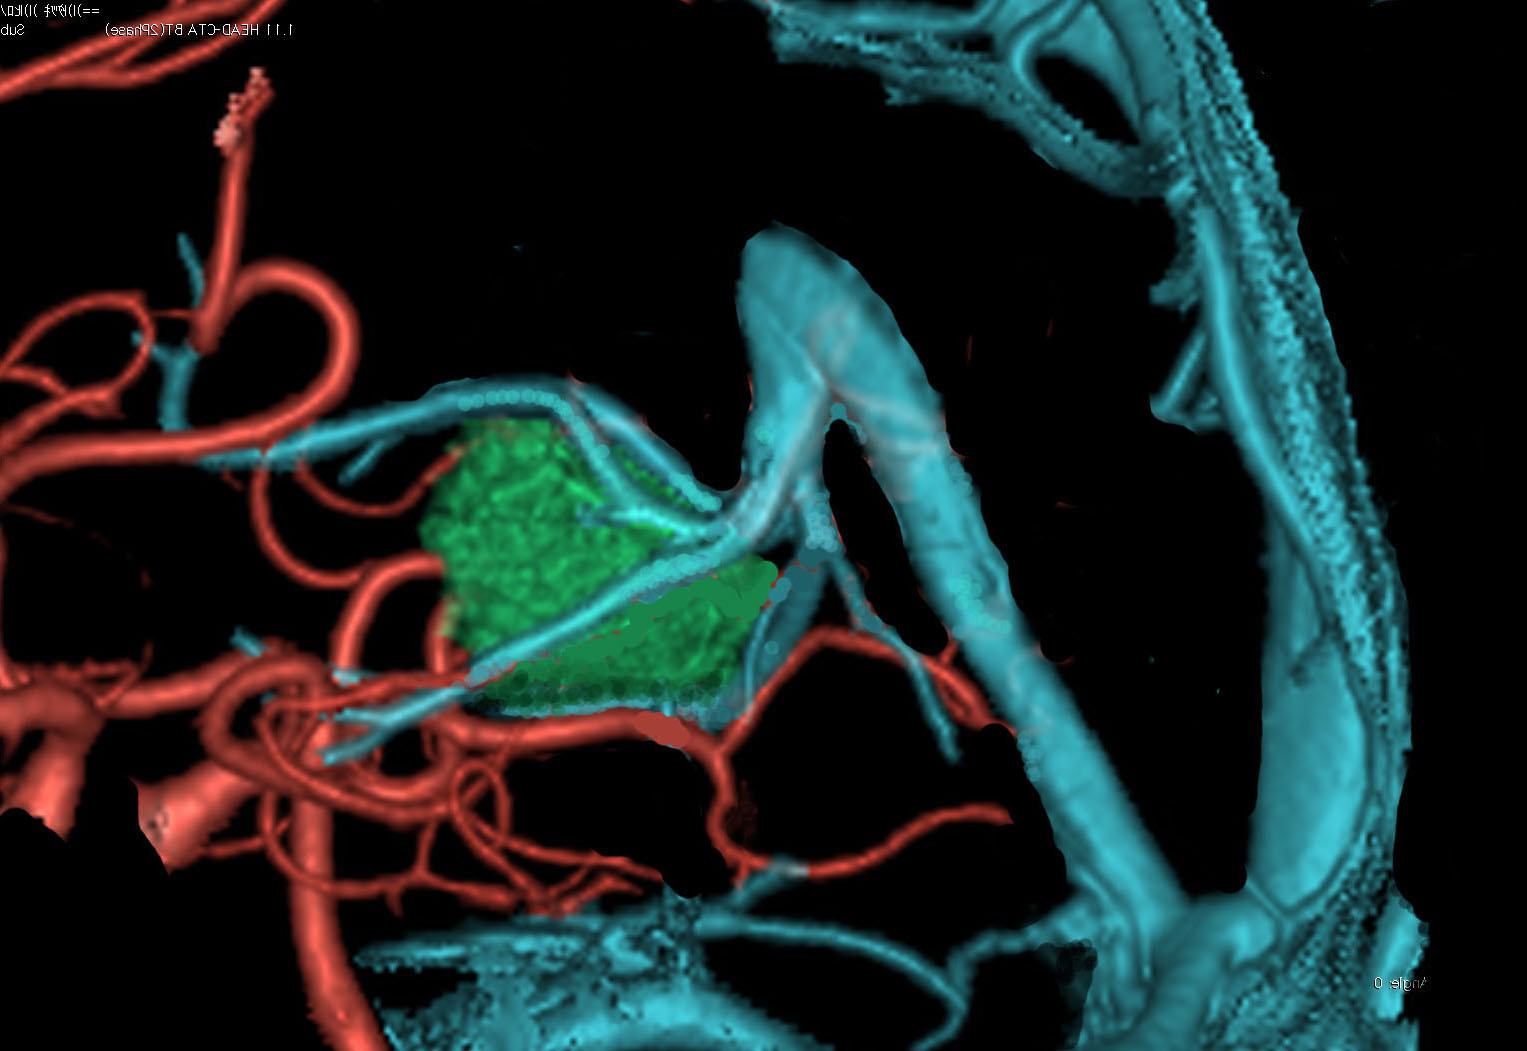

松果体腫瘍へのOTAのルートです。occipital transtentorial apporachというのは黄色の矢印に沿ってガレン大静脈の下に入る方法であり,そこから松果体部を通って第3脳室内へ直線的な視野が展開します。

一方,赤の矢印に沿ったルートは parieto-occipital transtentorial approachです。このルートでは内大脳静脈 internal cerebral veins を見ることがかなり難しいです。更に,第3脳室に入るためには脳梁膨大部 spleniumを切断する必用があります。ただし,小脳上部や第4脳室を見るときにはparietal寄りのルートを使います。

OTAでこの奇形腫を見ようとする場合に,テントを静脈洞交会の低い位置まで切断しなければ,直静脈洞の横から松果体部をみることはできません。また,黄色の矢印の方向に視野が入るので,まず最初に邪魔になるのは小脳上極です。上小脳層を左右ともに十分剥離すると,小脳が可動化して,その向こうに,precentral cerebellar veinが見えます。このveinをガレン大静脈への流入部から小脳前面に沿って剥離していくと,小脳上極がさらに可動化して松果体への視野が開ます。

松果体腫瘍の手術では,中脳背面を見る必要があります。特に上丘とそれに連続する後交連 posterior commissureを十分に観察するために周囲組織の剥離を行います。具体的には迂回槽と下丘の周囲のクモ膜組織を剥離します。対側中脳と迂回槽を見る時に妨げになるのが,緑の矢印で示した直静脈洞です。テントが長く切断してあって直静脈洞が大脳鎌と一緒に動かせると対側を見るのがとても簡単になります。

ガレン大静脈に流入する内大脳静脈 ICVとローゼンタール静脈とprecetral cerebellar veinの位置関係を俯瞰した図です。この例ではガレン大静脈と直静脈洞の接合部が高い位置にあります,galenic pointが高い,あるい接合部がsteep angleであると表現します。個人差が大きいものですが,galenic pointが高い方がガレンの可動性が大きくて手術はしやすいといえます。